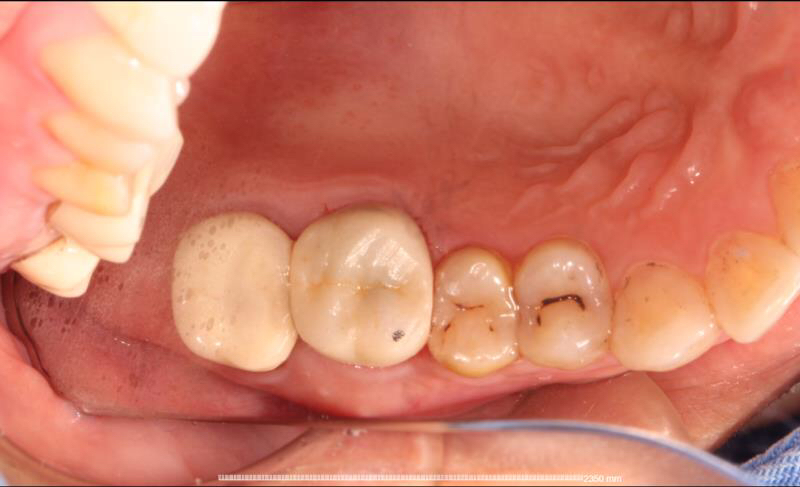

患者中年女性,右上6外院根管治疗多年,近期牙龈红肿,咀嚼疼痛,X线检查见根尖区大面积低密度影响,怀疑有遗漏的根管没有清理,用铒激光无损拆掉牙冠后进行根管再治疗,找到了遗漏的MB2,妥善的根管治疗完成后,重新戴上之前拆掉的牙冠,即解决了疼痛又为患者节省了一笔费用。